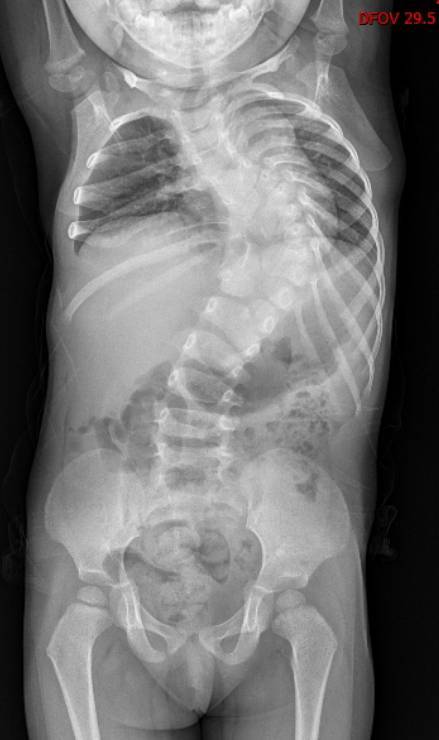

女童可可(化名)家住新洲,先天性椎体发育畸形。自出生起,她的脊柱就向左倾斜,整个身体异常扭曲。随着成长,弯曲日益加重。2岁时,可可脊柱倾斜度数已达到90度——上半身几乎被“折”成了直角。可可四处求医,可都因为畸形严重且复杂,矫形难度大,年龄小且治疗周期长,未来治疗存在不可预测性,迟迟没能得到有效救治。

“如果把脊椎比作一栋大厦,她的第5胸椎到第3腰椎,一共11个脊椎就像11层楼,成了一片废墟:有的‘楼层’合并,有的被拆成两半,有的缺失‘墙体’,没有一处是正常的。”周治国这样形容。

2015年,2岁半的可可在武汉儿童医院接受了一期手术。专家在可可的胸椎和腰椎上植入了4根生长棒和8枚椎弓根钉当“支架”,尽可能多地给扭曲的脊柱以支撑,延缓脊柱侧弯的进展,同时为胸腔和内脏争取生长空间。

时间一天天过去,可可一点点长大,在医生的控制下,她脊柱侧弯度数从90度降至72度,这也为终末期矫形手术争取到了机会。

2025年,可可年满12岁,胸腔、胸廓已基本发育成熟。周治国团队决定是时候对最严重的顶椎“动手”了。医生利用3D打印技术,1:1还原了畸形脊柱的脊柱模型,制定了截骨矫形的手术方案。

整场手术足足进行了10个多小时,周治国团队避开脊柱周围的神经和血管,对可可畸形弯曲最严重且最突出的顶椎进行截骨、重整、固定。当手术进入尾声时,可可脊柱的侧弯度数从72度改善至30度,可像正常人一样生活。